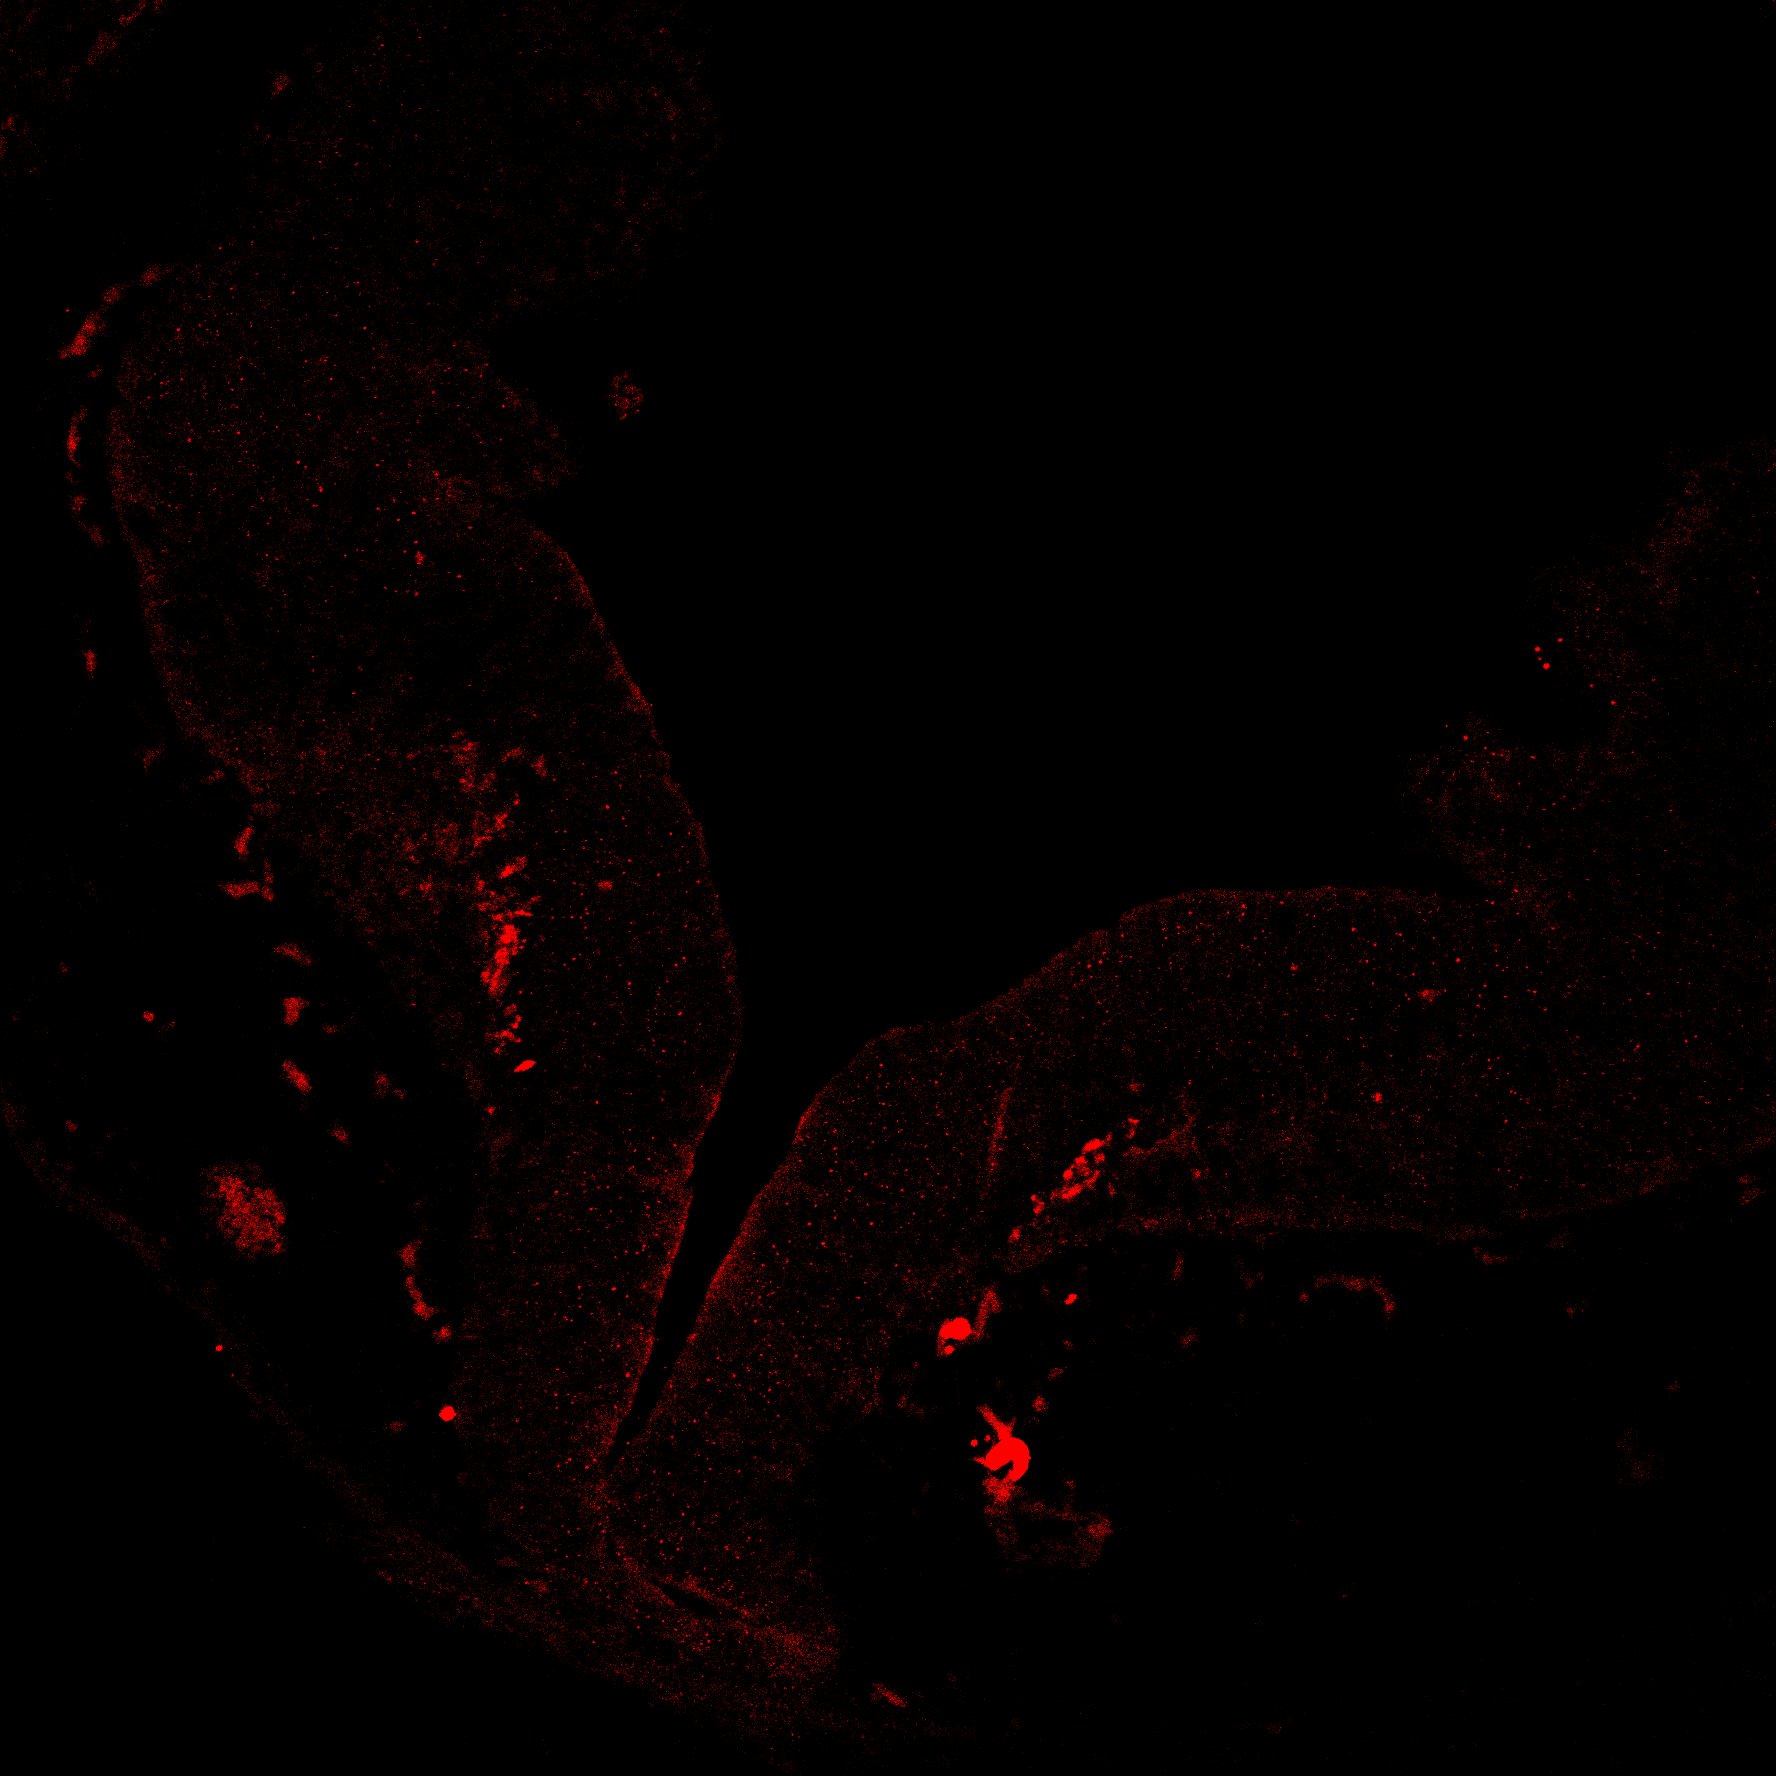

An in vivo and in vitro spatiotemporal profile of human midbrain development

An anatomical analysis of the developing human midbrain from 6 post-conceptional weeks (PCW) to 22 PCW reveals increased tissue complexity, characterized by the emergence of dopaminergic nuclei, as highlighted by immunofluorescence analysis for tyrosine hydroxylase (TH).

TH

6PCW human midbrain